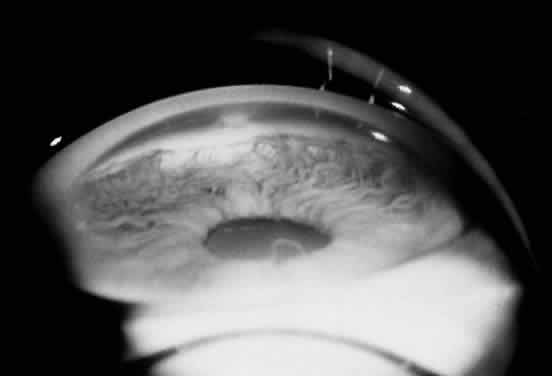

POSTERIOR KERATOCONUS

Posterior keratoconus is a rare corneal disorder characterized by a localized craterlike defect on the posterior corneal surface, with the concavity facing toward the anterior chamber (Fig. 9).111 The anterior corneal surface is normally sculpted. Vision may be normal or slightly reduced. Reduced vision may be secondary to scattering of light from the irregular posterior surface, or to a steepening of the anterior cornea in the region of the posterior defect.112 Posterior keratoconus may be either unilateral or bilateral. It is frequently nonfamilial, although it has been described in a parent and sibling in three families and in siblings in another family.111,113,114

Fig. 9. Posterior keratoconus. A. Direct illumination. B. Slit-lamp image demonstrating the concave defect. (Courtesy of James J. Reidy, MD)

Histopathologically, Descemet's membrane is present but may show thinning, abnormal anterior banding, and posterior excrescences.111,115 The endothelium is intact but displays cytoplasmic vacuolation and attenuation adjacent to the posterior excrescences.111 Several theories have been proposed to explain the pathogenesis of congenital posterior keratoconus. Mann suggested that posterior keratoconus is caused by an arrest of corneal development and the resulting persistence of embryonal characteristics.116 Greene117 explained the origin of posterior keratoconus as the result of delayed separation of the lens from the cornea.